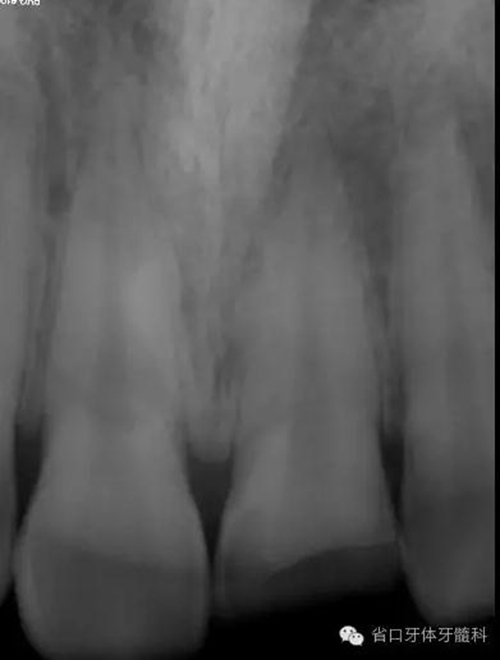

術(shù)前X線片

X線片示21冠折,根段未見明顯牙折影像。